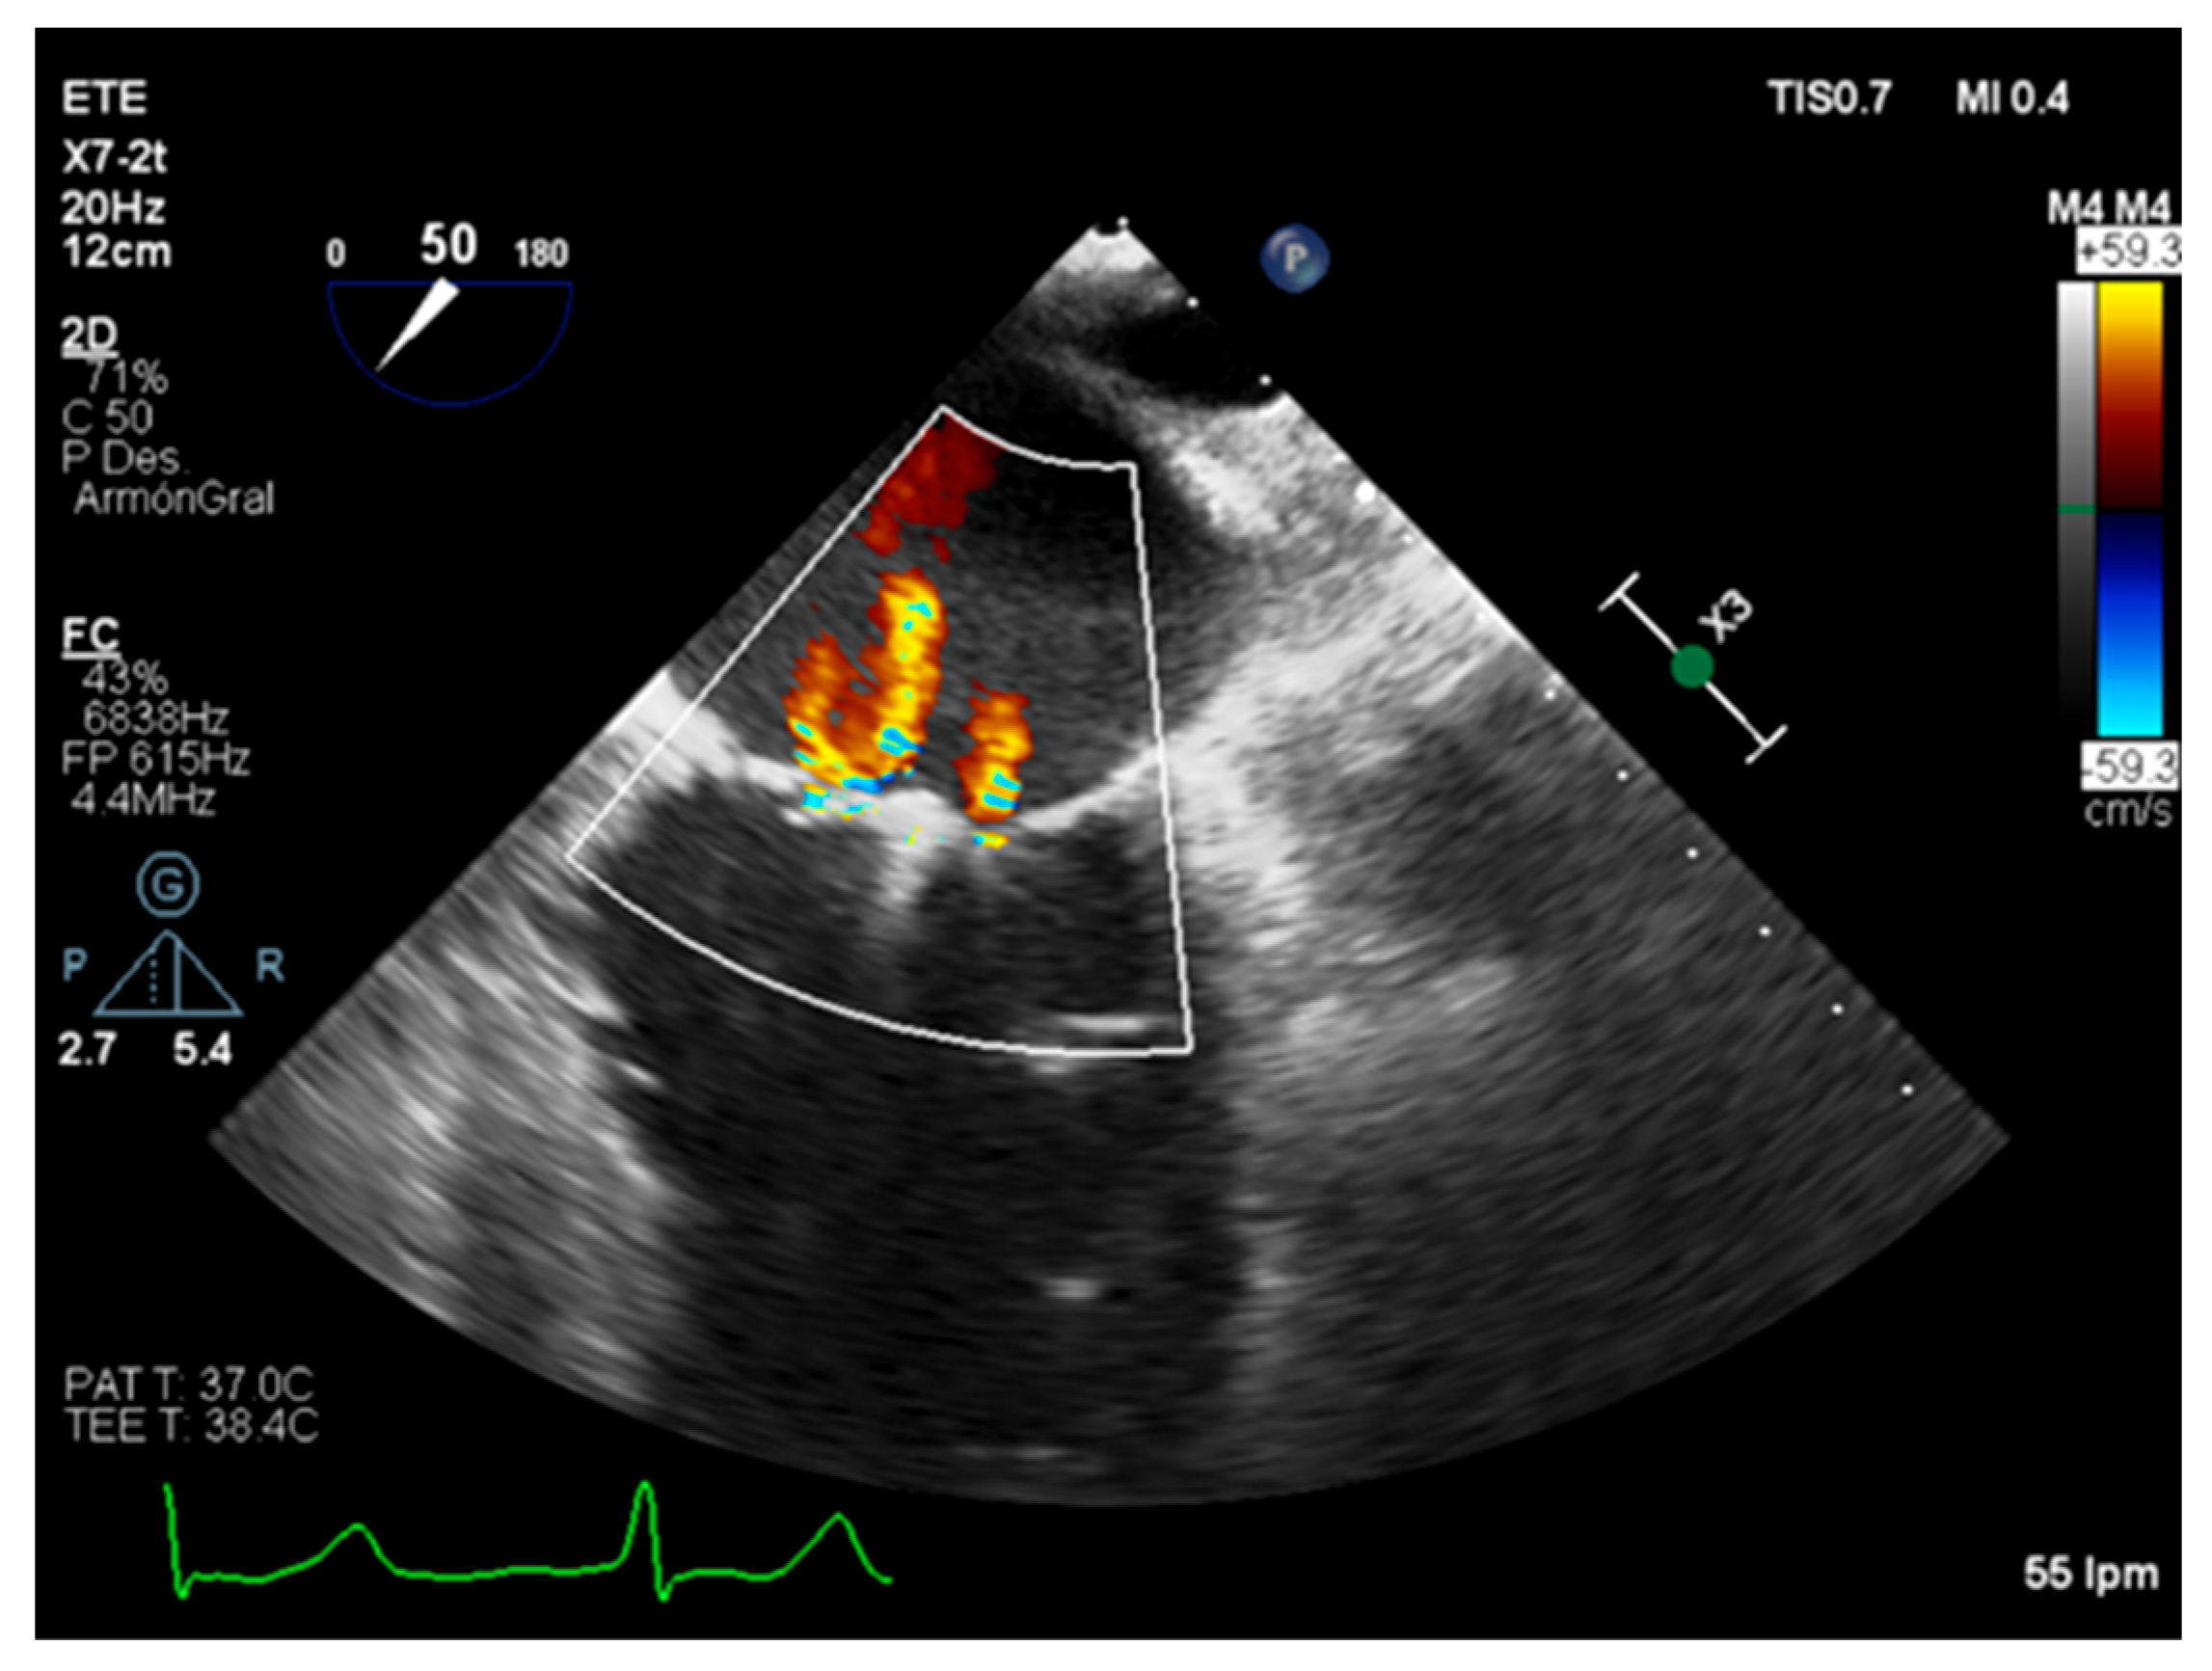

5. Role of Intraoperative Echocardiography

| Color flow jet | Qualitative. | Small, central. | Large central jet or eccentric reaching the posterior LA wall. |